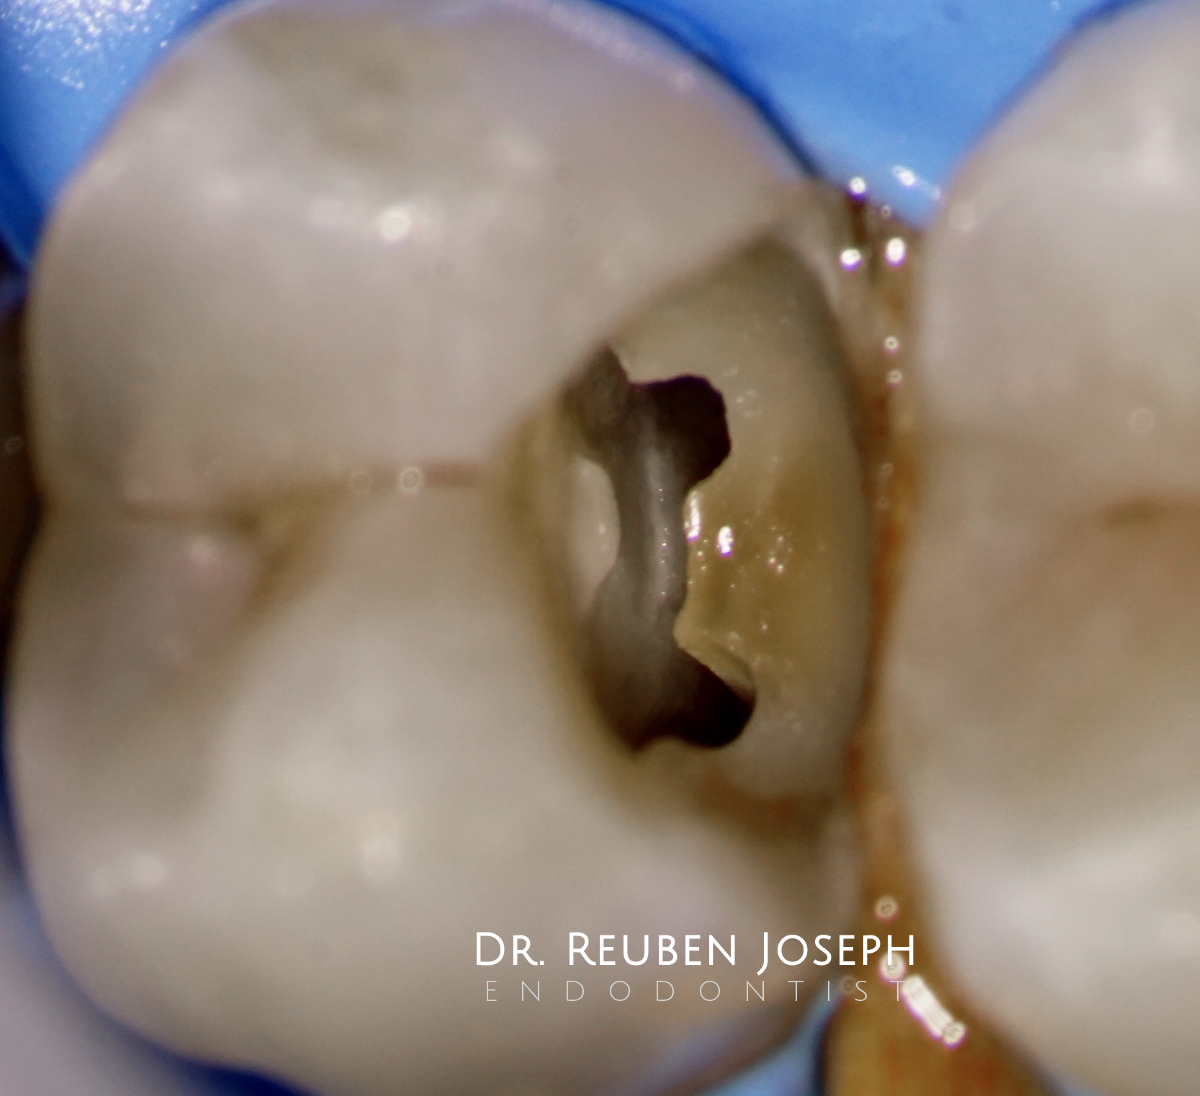

pulpchamber

Nothing  special. A few premolars i got to treat recently with access cavity designs specific to what the clinical scenario demanded.